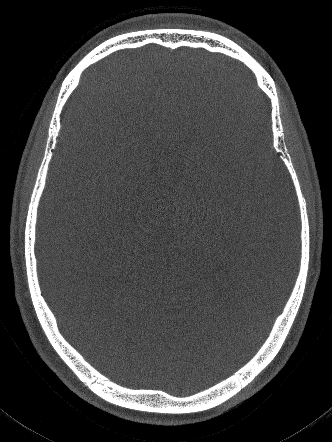

Figure 3 compares the proposed network-based IQM with the entropy-based IQM. The optimization process is identically for both metrics. In an inverse crime scenario both methods can restore the original image quality, however, in a more realistic setting the image entropy is stuck in a local minimum, whereas the network is able to lead the optimization to a nearby motion-free solution.

Refer to captionGt Refer to caption Mo a Refer to captionEnt Refer to captionPro a Refer to captionEnt Refer to caption Pro

Ground Truth (Gt) and Motion Affected Inverse Crime Compensation Clinical Setting (Entropy and Proposed)

Figure 3: Reconstructions of the test patient using [500-2000] HU window. In the inverse crime scenario, the SSIM to the Gt is 0.840.840.84 (Ent/Gt) and 0.950.950.95 (Pro/Gt), respectively for the entropy (Ent) and proposed (Pro) measure. For the more realistic setting (Clinical Setting) the SSIM is 0.650.650.65 (Ent/Gt) and 0.840.840.84 (Pro/Gt), respectively.